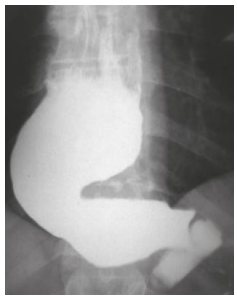

Mulher,56 anos, portadora de megaesôfago grau IV (imagem abaixo). Admitida na enfermaria com desnutrição grave. Após instalação de sonda nasoenteral e dieta, passou a apresentar exames laboratoriais compatíveis com síndrome de realimentação.

Após realizar um ionograma, qual alteração foi identificada?